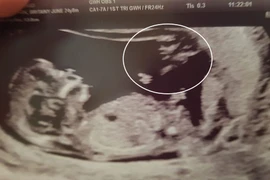

(Kiến Thức) - Khi nhìn kỹ vào bức ảnh siêu âm thai của mình, cô Britainy phát hiện, bên cạnh hình ảnh của con yêu, có bóng dáng kỳ lạ góc bên phải bức ảnh, bóng dáng này có hình ảnh như một thiên thần đang chỉ tay vào em bé.